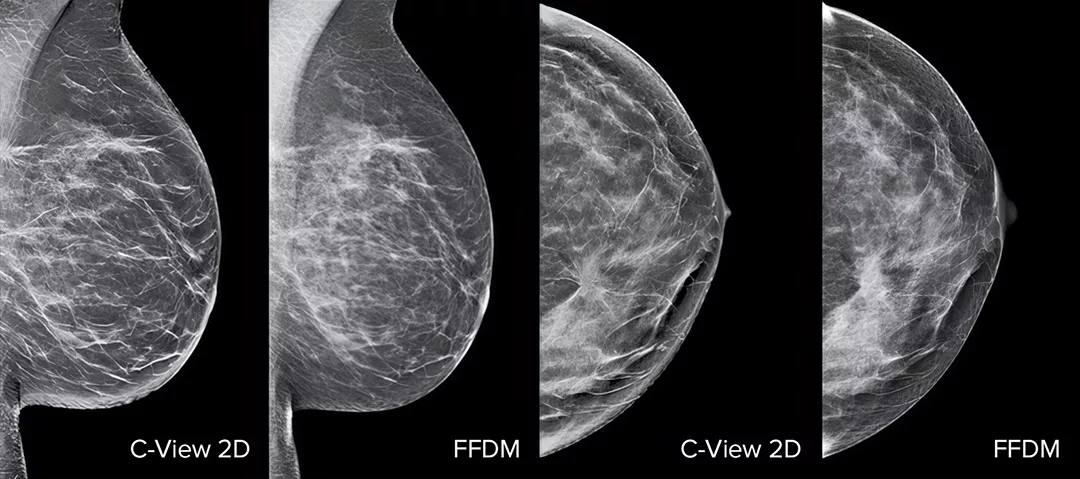

Gør brystkræftscreening bedre1-4 med C-View-softwaren og øjeblikkeligt genererede syntetiserede 2D-billeder. Det forbedrer ikke kun detaljerne og øger analysehastigheden, men reducerer også stråledosisniveauet for dine patienter. C-View 2D-billeder er klinisk dokumenteret3,5 og FDA-godkendt til diagnostisk at erstatte FFDM-billeder i en tomosyntese-screeningsundersøgelse.

Arkitektoniske forvrængninger, masselæsioner og lyse pletter, der ofte findes i mikroforkalkninger, er mere synlige på C-View 2D-billedet end på de traditionelle FFDM 2D-billeder eller tomosnit.4,6-9

C-View 2D-billeder er klinisk dokumenteret3,5 og FDA-godkendt til diagnostisk at erstatte FFDM-billeder i en tomosyntese-screeningsundersøgelse. Billederne fungerer også som en navigationshjælp ved gennemgang af tomosyntesesnittene. Offentliggjorte forsøg viser, at undersøgelsen med 3D-mammografi med lav dosis finder invasiv kræft tidligere og samtidig reducerer antallet af falsk positive genindkaldelser sammenlignet med 2D alene.4,5,7

Arkitektoniske forvrængninger, masselæsioner og lyse pletter, der ofte findes i mikroforkalkninger, er mere synlige på C-View 2D-billedet end på det traditionelle FFDM 2D-billede eller tomosnit.4,6-9